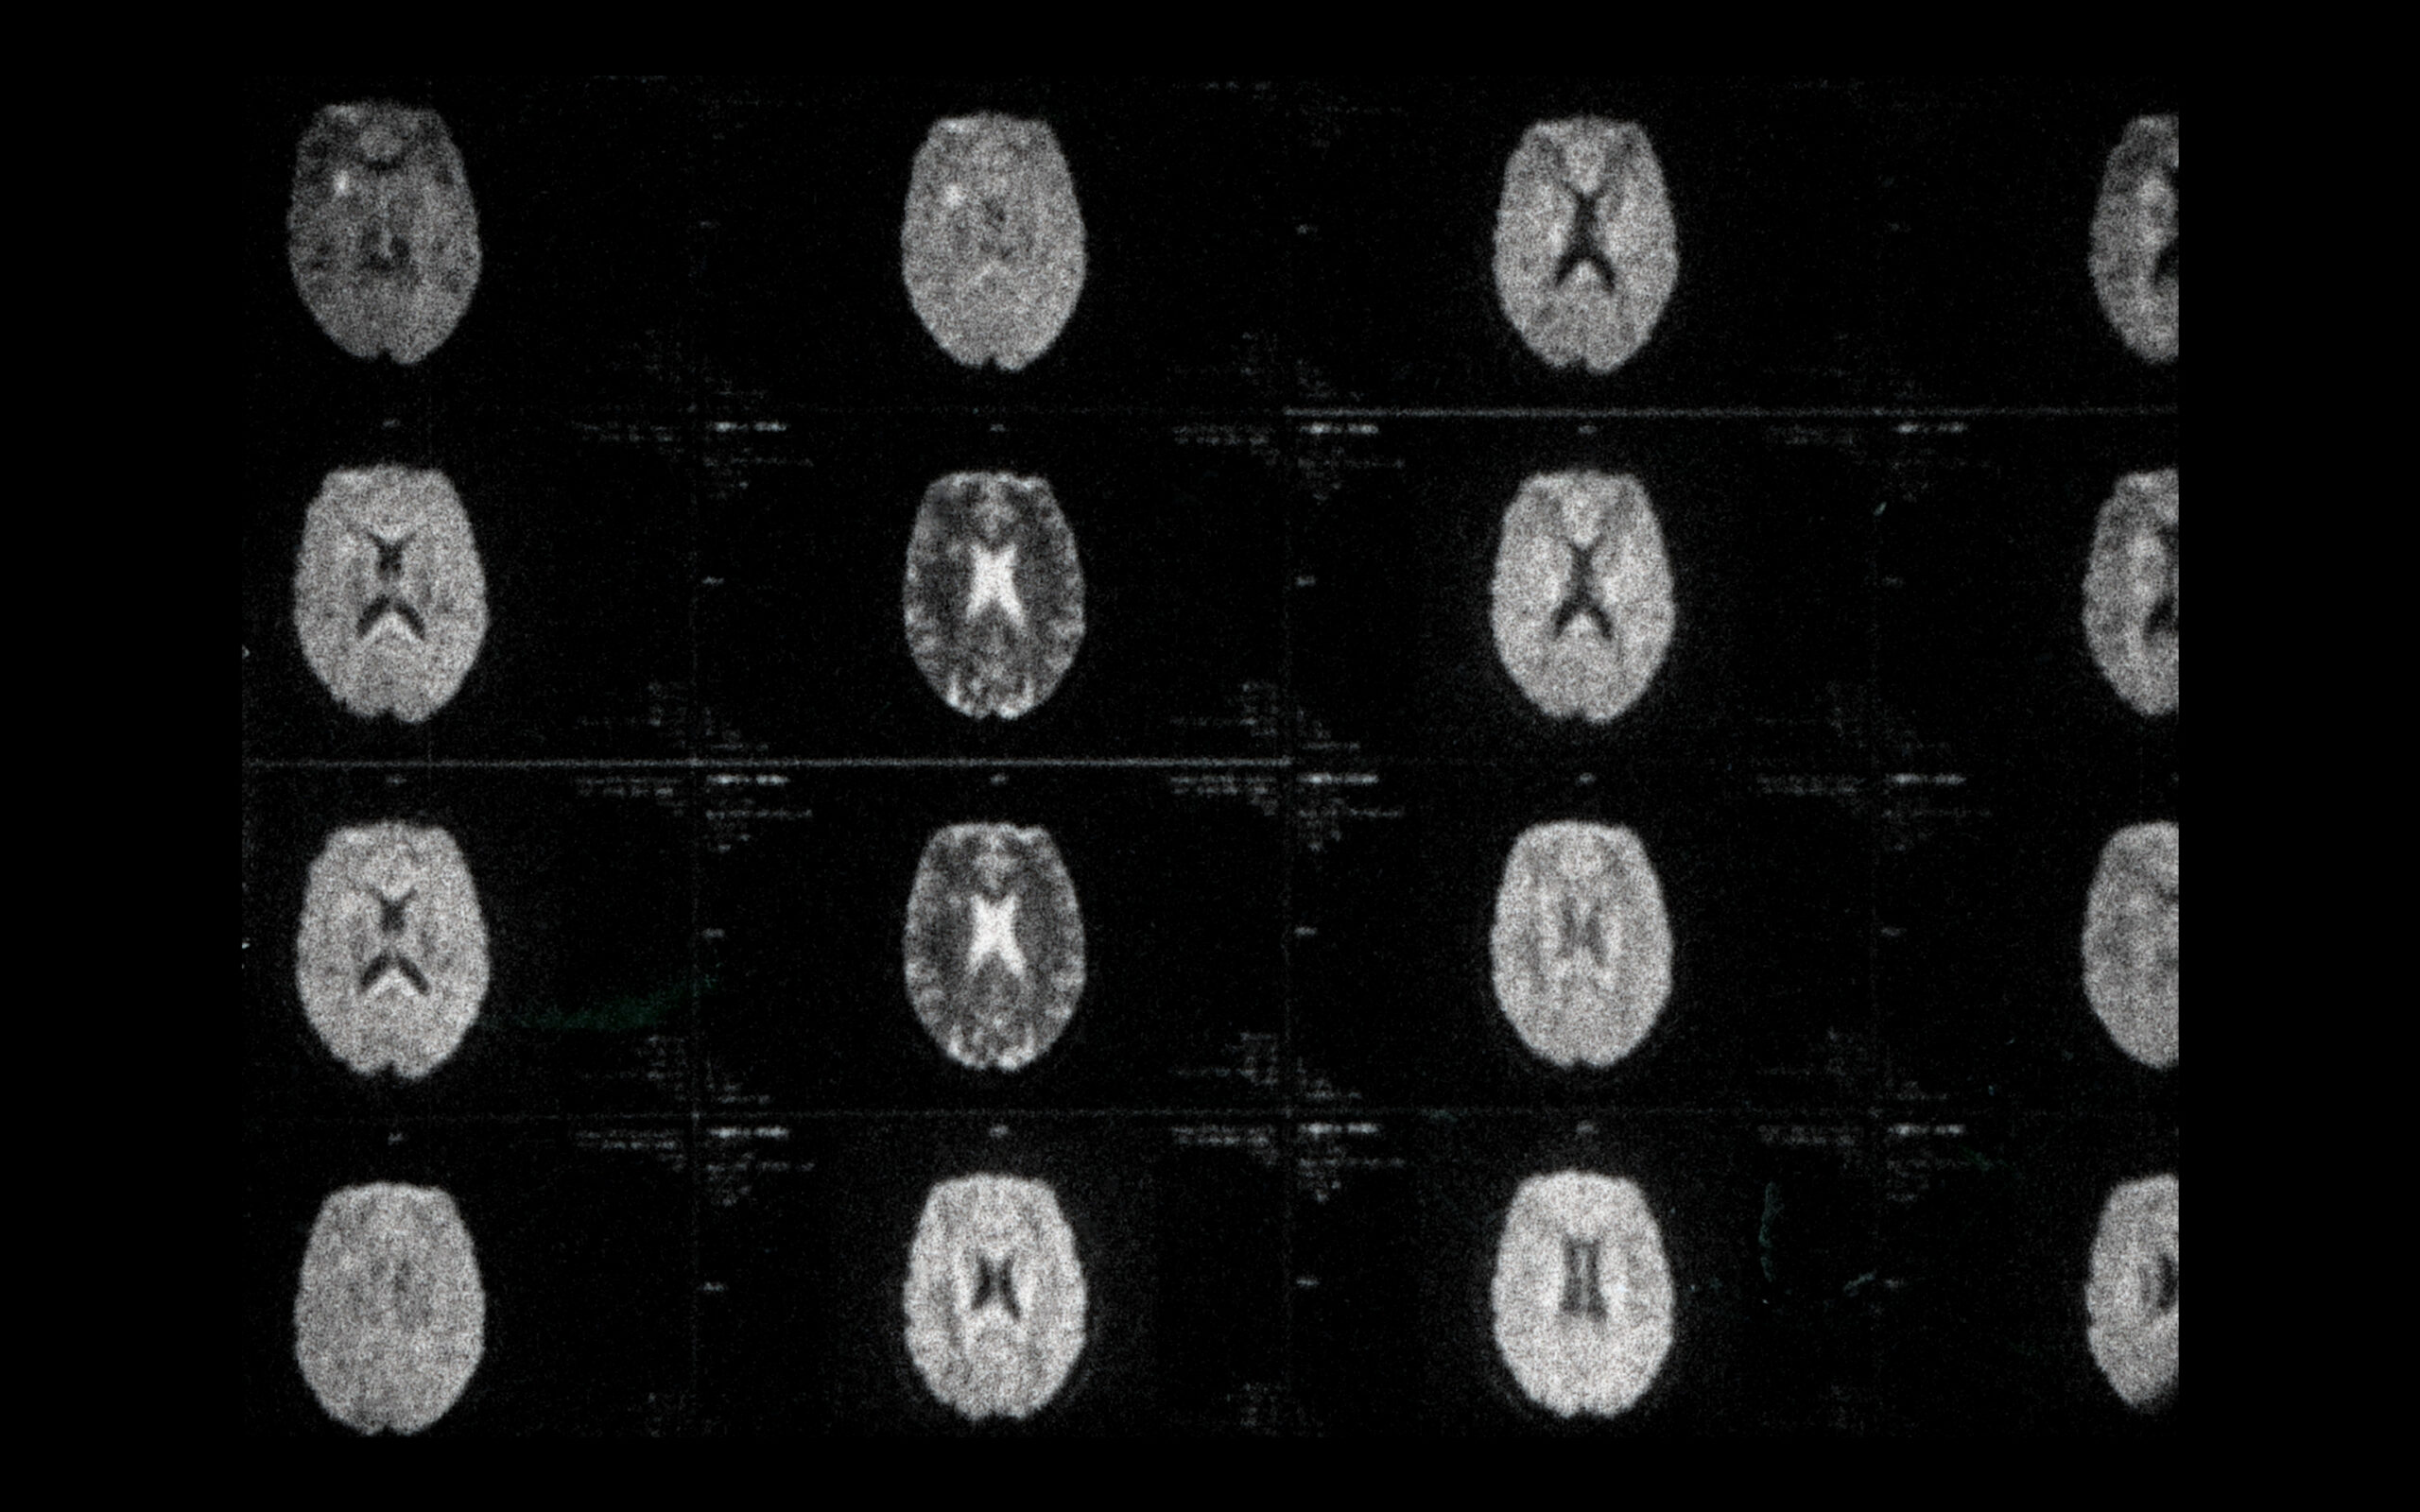

In IN MY HEAD the filmmaker reflects on her multiple sclerosis by examining her own magnetic resonance images, thus sketching the movement of life that persists with the disease.

Filmmaker Irina Tempea has become one with her film, a small diary about the multiple sclerosis she suffers from. Filmed on shaky and “dirty” celluloid, the documentary translates its content perfectly into form, each artifact seeming to bear the imprint of morbid anxiety, each analog tremor a struggle. Looking at the disease from the inside (X-rays) and from the outside (glimpses of everyday life), synchronizing, desynchronizing, and resynchronizing the speed of radiology with the slowness of the sick body, IN MY HEAD offers a great deal of human understanding and an artistic interpretation of the self as a patient. (Călin Boto)